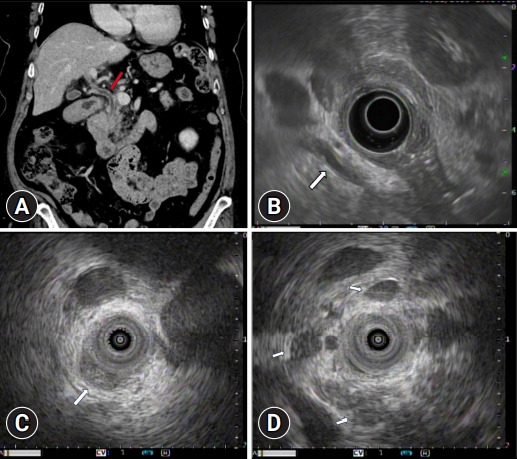

Pancreatic heterotopia mimicking a common bile duct tumor.

模拟胆总管肿瘤的胰腺异位。